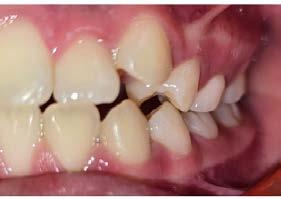

Se observó en la evaluación asimetría facial, tercio inferior aumentado, en la regla de quintos las líneas interpupilares no coinciden con la comisura labial, muestra 2/3 de las coronas superiores al sonreír y perfil retrusivo ocasionado por la distoclusión mandibular (Figura 1).

Su fonación no es clara, ya que presenta congestión nasal y hábito de lengua. Las fotografías intraorales de inicio se muestran en la Figura 2

Figura 2. Fotografias intraorales: A) fotografía de en oclusión, mordida abierta, línea media desviada. B) fotografía lateral, clase II subdivisión I.